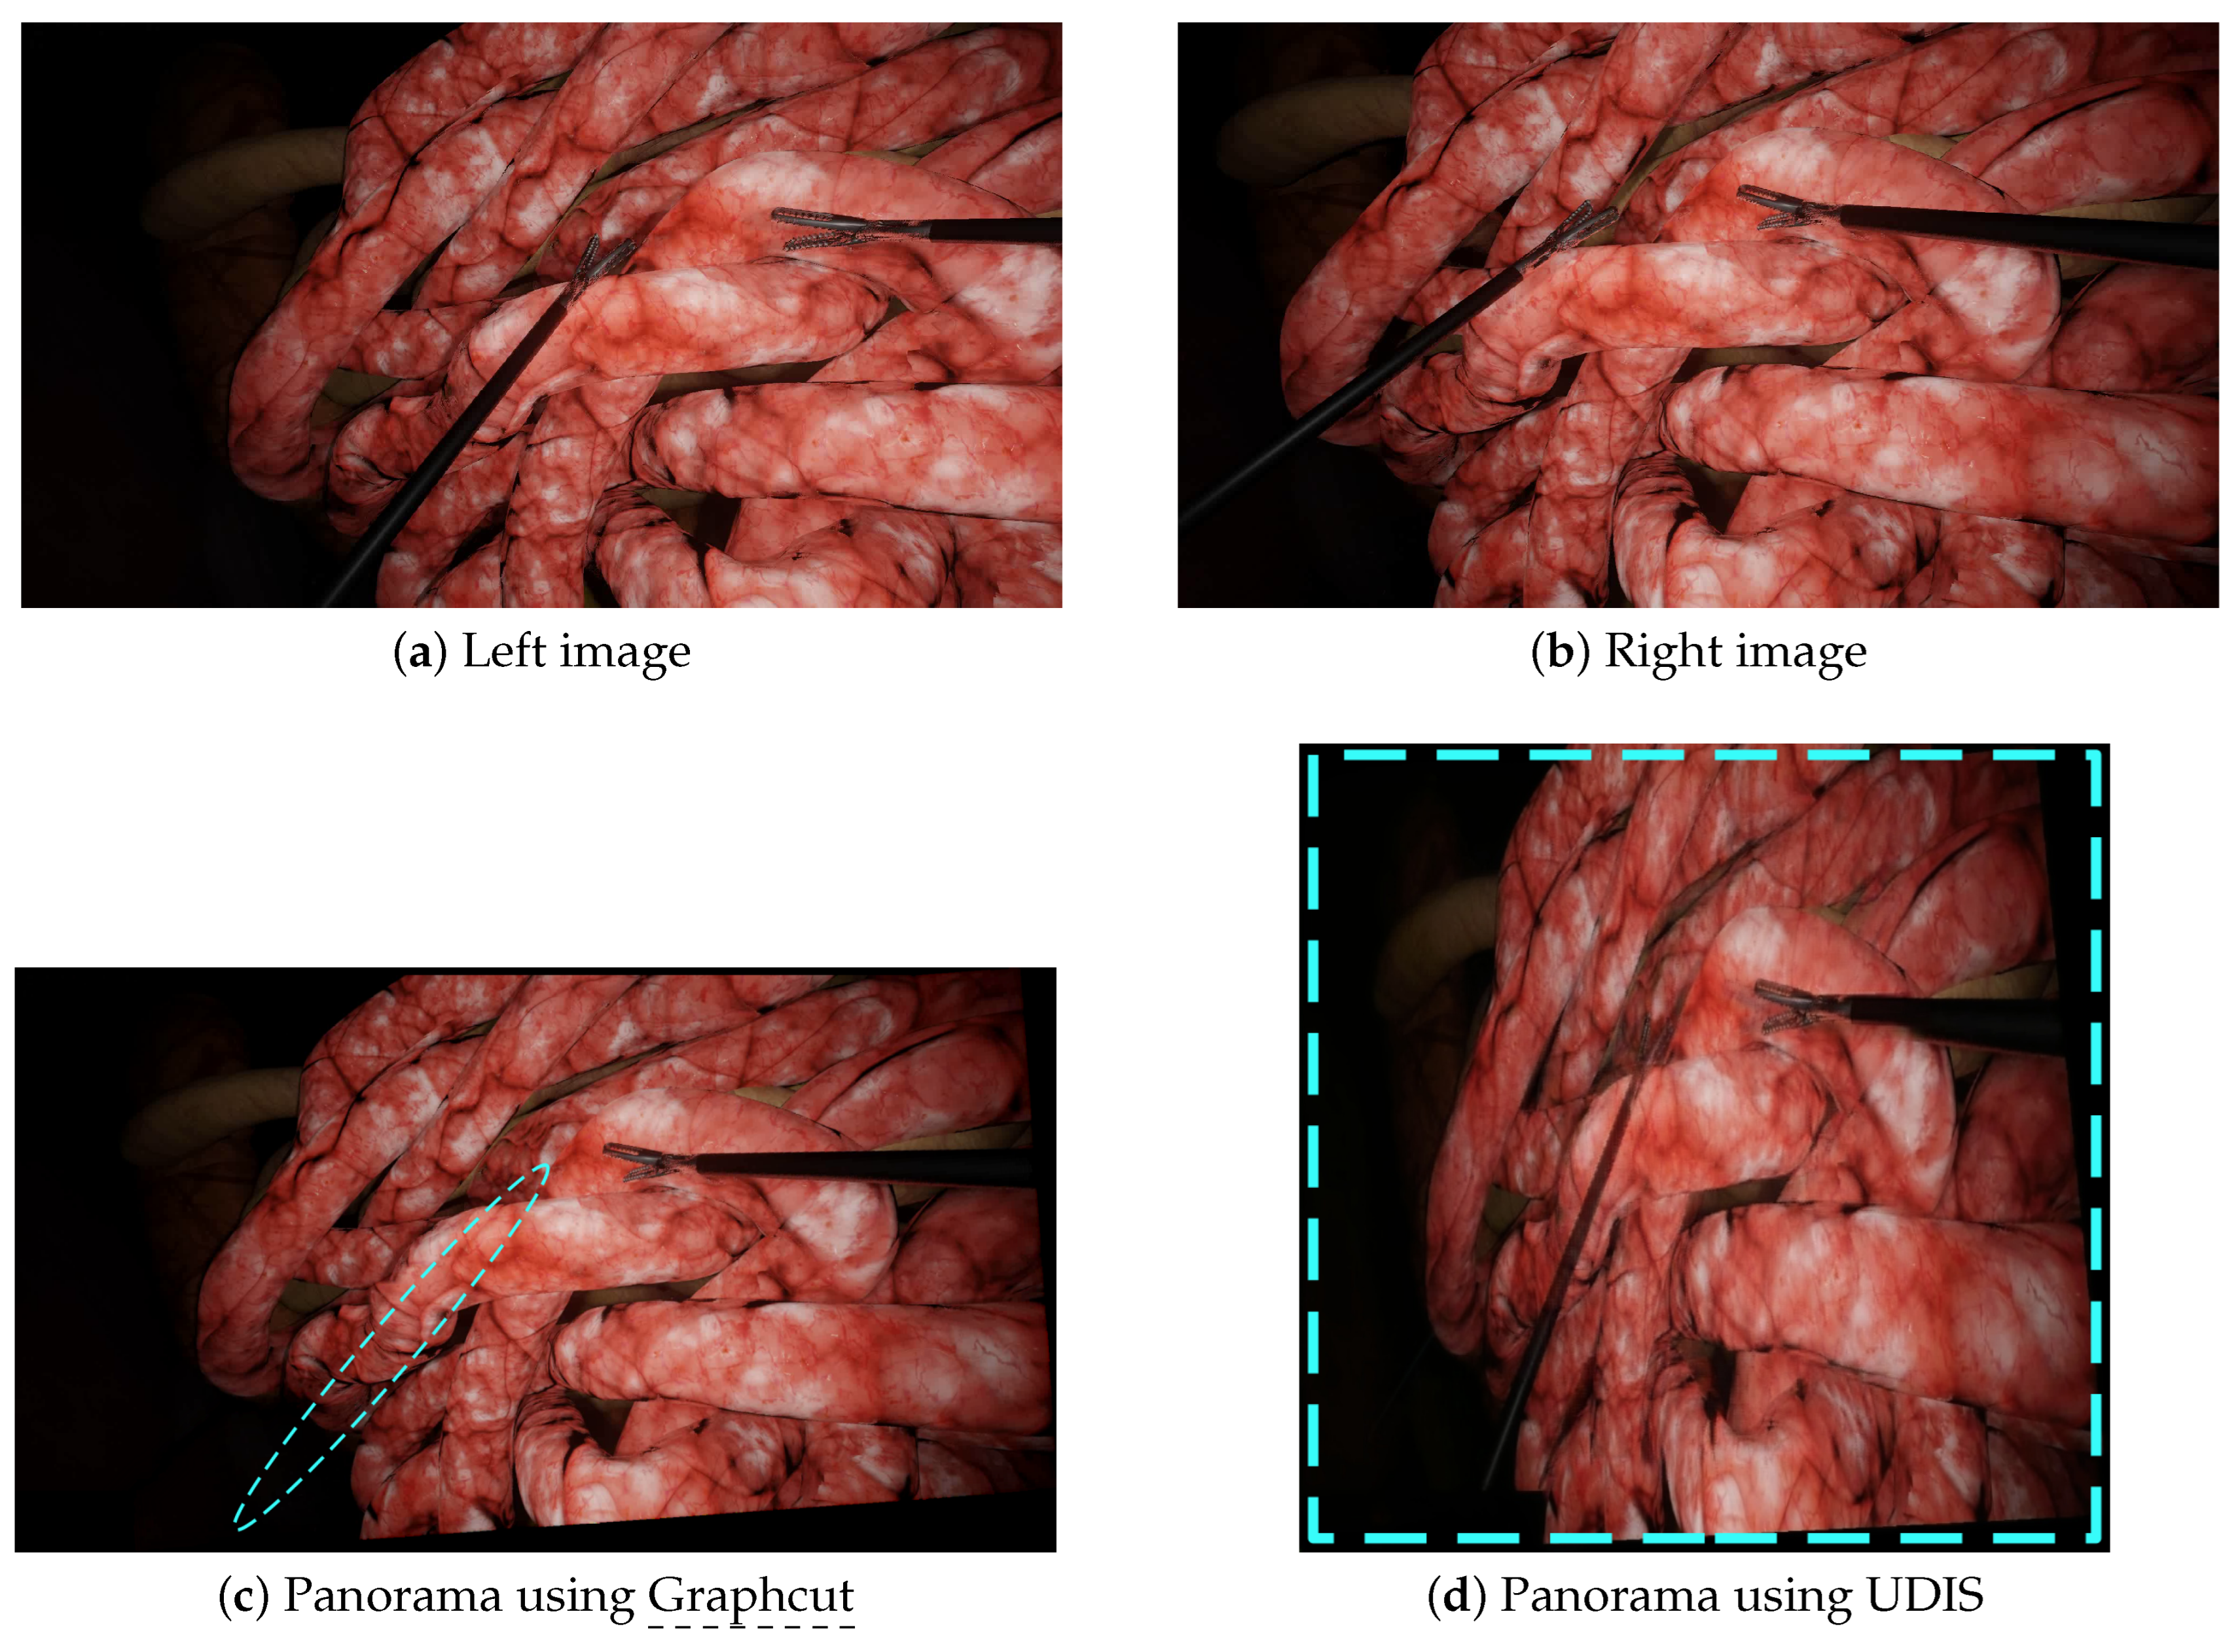

Figure 6.

A scenario with more parallax: the left (a) and right (b) images were stitched together by Graphcut and UDIS. (c) With Graphcut, only one tool was present in the final panorama while there were two tools in the input images. (d) With UDIS, the two tools appeared in the resulting panorama but with huge projective distortions. The blue dashed lines show the major issues (missing tools and distortions).

Figure 7.

A complex scenario with crossed tools: the left (a) and right (b) images were stitched together by Graphcut and UDIS. (c) With Graphcut, discontinuities appeared when the tools intersected in the input images. (d) With UDIS, a duplicated pair of forceps appeared in the bottom right corner.